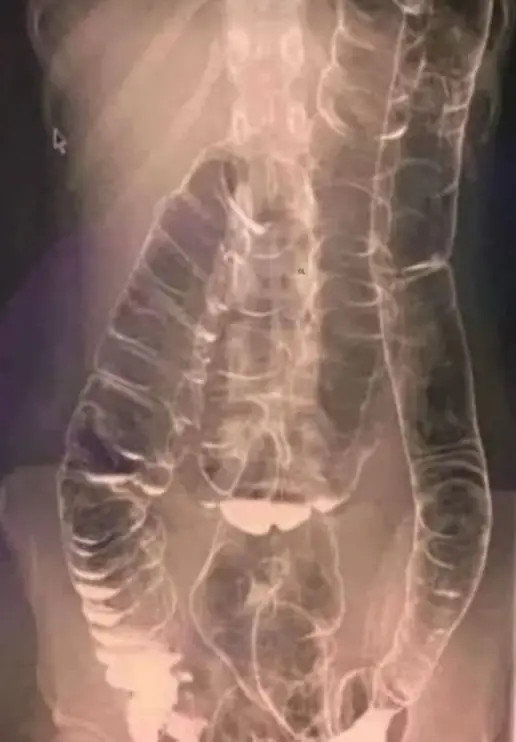

The definition of constipation often extends beyond the lack of bowel movements, encompassing the experience of abdominal pain, difficulty during bowel movements, and a sensation of bloating. A notable case reported in recent medical literature revealed an alarming X-ray of a woman who suffered two weeks of constipation. This situation shocked medical professionals as they observed her colon enlarge significantly, extending towards the chest, dangerously close to the heart. Such drastic changes in the digestive tract highlight the importance of addressing chronic constipation; the colon’s folds, which are essential for its normal functionality, may eventually disappear under prolonged pressure.

Several physiological changes stem from prolonged constipation. One significant issue is that the colon may lose its natural ability to compress and effectively push feces forward when it is compelled to extend beyond its normal limits. In a worst-case scenario, this can lead to toxins starting to seep into the bloodstream, causing a myriad of health problems including reduced immunity, persistent bloating, unpleasant breath, skin issues like acne, and even chronic fatigue. The connection between gut health and overall health cannot be overstated, as these toxins can trigger systemic inflammation, leading to more severe health issues over time.